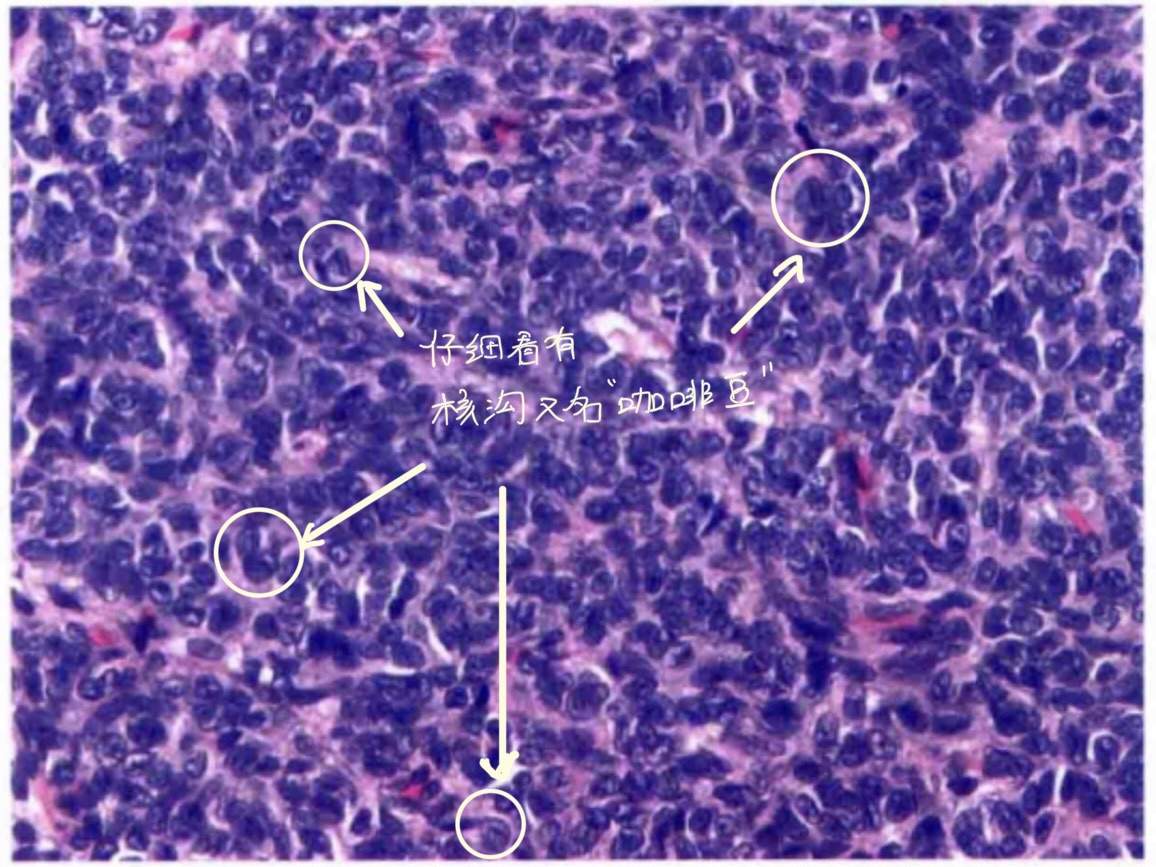

它有两个关键词:咖啡豆样的核和Call-Exner小体,看图:

粒层细胞瘤的另一个特点就是细胞核大小比较一致(和生殖细胞肿瘤比起来胞核比较大且染色也没有那么细腻);肿瘤内间质成分比较少(这一项是对比Sertoli-Leydig细胞瘤,后者肿瘤内有大量的间质成分);还有一个必须要鉴别的是卵泡膜细胞瘤(网状纤维染色)。